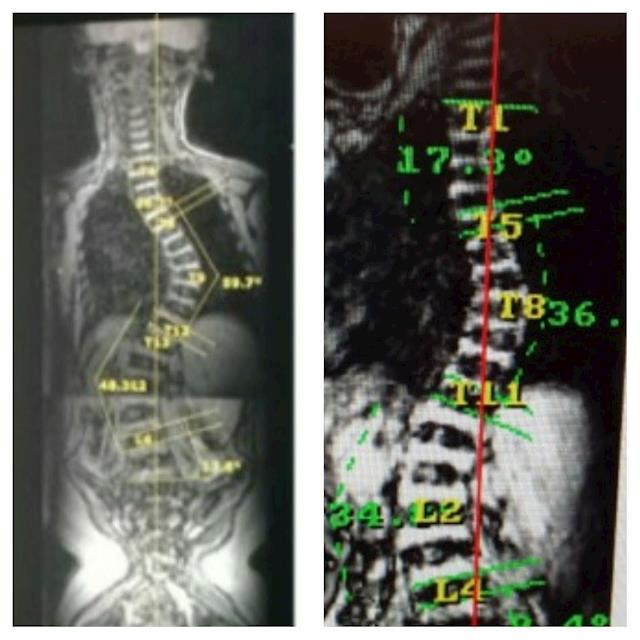

Caitlin has just returned with two other kiwi friends from the Scoliosis Care Centre in California. Yes we've just been back again! 6 months. 3 trips. We are over the moon with her results so far, her largest curve at 60 degrees is now just 36! Her bottom curve is now just 34 degrees! Yes nearly half its size in just six months. Six hard, expensive, draining months. But worth every single cent. Worth every single tear and every single drop of sweat. Caitlin is now officially out of surgery range 🎉🎉🎉 something that seemed completely impossible just 6 months ago!!

Caitlin's condition has 100% of progressing rapidly due to her age and her curve is already and S shape with 55 at the top and 50 degrees below (it was 45 and 42 degrees when we discovered it in February this year). She is wearing a back brace 20+ hours a day to try and hold the curve while we work towards this treatment plan. It's so painful for her both physically and emotionally, but we're so very proud at how well she is adjusting to the brace and coping with the emotional toll of this disease.